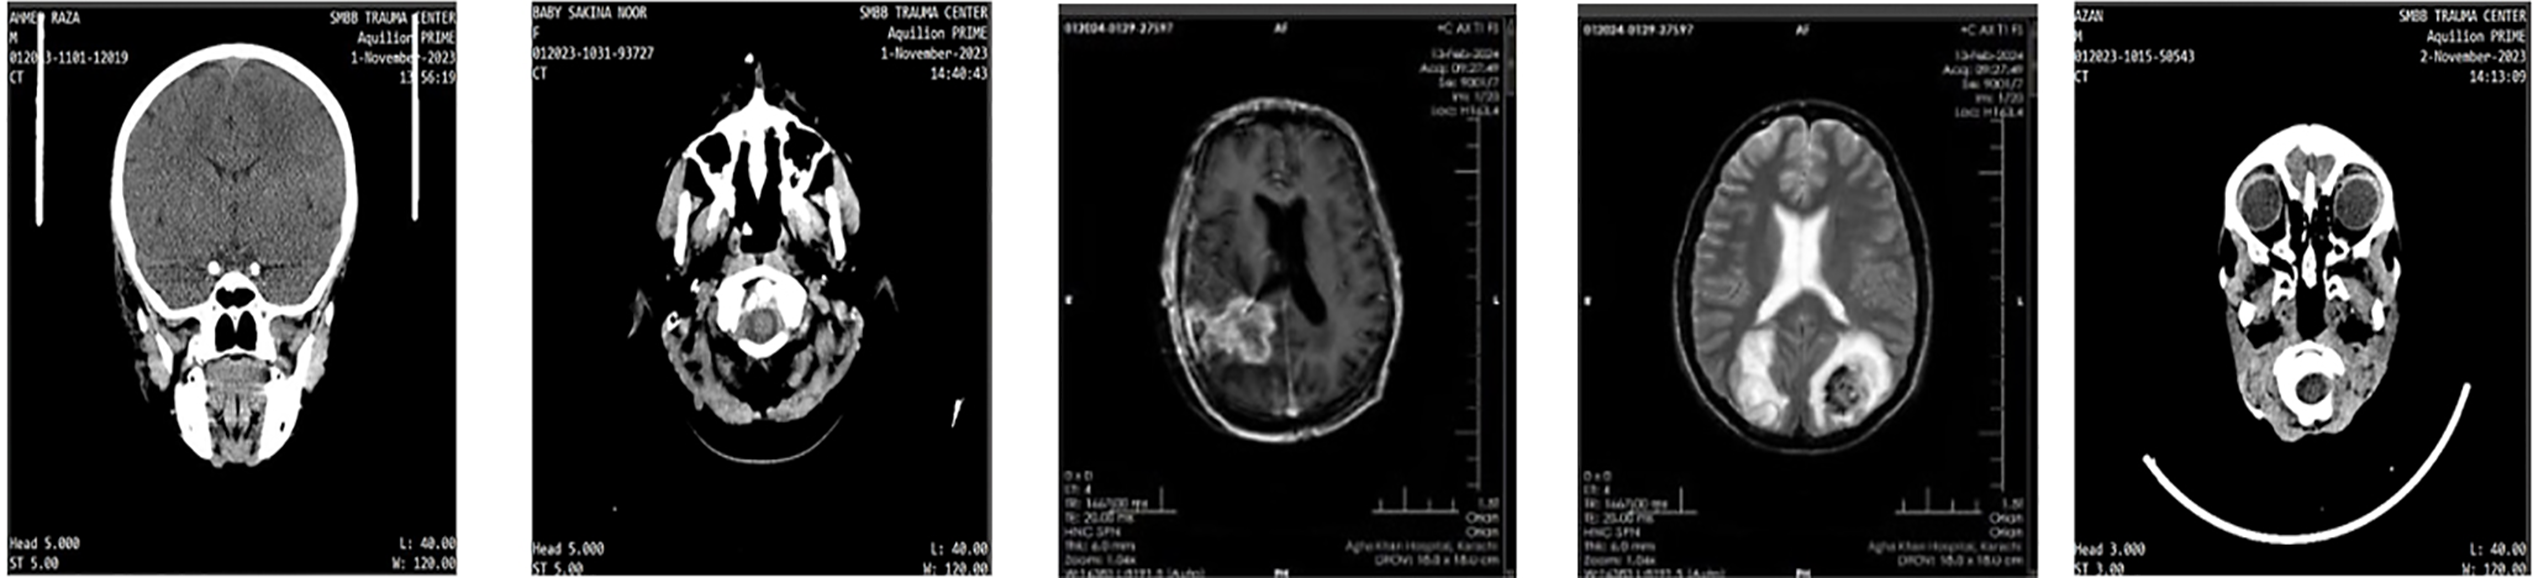

The proposed model was trained and evaluated using the Figshare brain MRI dataset introduced by Cheng et al. [38]. This dataset contains 3065 MRI slices from 233 patients and was selected for evaluation since it is commonly used in related studies for performance comparison. It includes three categories of brain tumors: pituitary (931 samples), meningioma (708 samples), and glioma (1426 samples). We additionally validated the proposed Fine-Tuned EfficientNet-B6 model on a private MRI brain tumor dataset to further evaluate its robustness and generalization ability. Fig. 1 presents sample images of custom BT datasets.

Figure 1: Sample images of the custom BT dataset